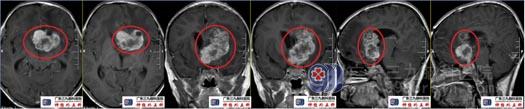

术后复查头颅CT示原病变已切除,术区示片状低密度影,间杂散在斑片状极低密度积气影,周缘示条状高密度影。

术后复查头颅MRI示原病灶切除满意。